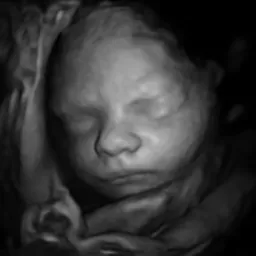

Examples

See a sneak peek of your baby

Transform 3D ultrasound images into stunning, photorealistic baby photos. Upload, customize, and receive a gallery of baby photos in minutes.

100% AI Generated Results

AI-GENERATED